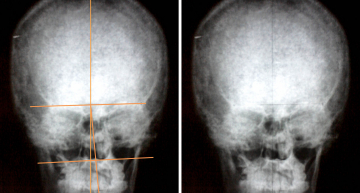

- Рентгенограмма — более точный метод, фиксирует правильность развития и положения позвонков.

- рентген. Один из самых простых и доступных способов диагностики кривошеи. Позволяет оценить наличие костной деформации в области шеи и черепа;